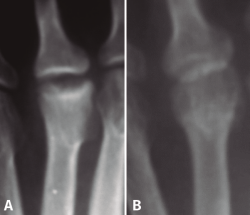

- Osteotomía del metatarsiano: tanto las osteotomías como las queilectomías se basan en el hecho de que, en esta enfermedad, casi siempre es posible encontrar una zona central-plantar de la cabeza del metatarsiano con un cartílago en buen estado. Esta osteotomía fue descrita por Gauthier(15) y tiene como objetivo cambiar la orientación de la zona de carga de la superficie articular (Figuras 7 y 8). Para ello se realiza la osteotomía en el cuello y se extrae una cuña de base dorsal. Se trata de una técnica ampliamente utilizada y se han publicado(25,26) buenos resultados con ella. De todas maneras y, a pesar de que se trata de una técnica sencilla, puede presentar una serie de complicaciones(27,28): metatarsalgia de transferencia, cuando se acorta excesivamente el metatarsiano, dedos flotantes y problemas inherentes al sistema de fijación: las agujas pueden migrar, las grapas pueden hacer una protuberancia en el dorso de la articulación y los tornillos pueden aflojarse, al ser muchas veces el hueso de mala calidad.

Figura 7. Esquema de la osteotomía de Gauthier: se extrae una cuña de base dorsal a nivel del cuello, con lo que se cambia la orientación de la superficie articular.

Figura 8. Osteotomía de Gauthier: A: preoperación; B: 2 años postoperación. Cortesía del Dr. F. Cabañó.